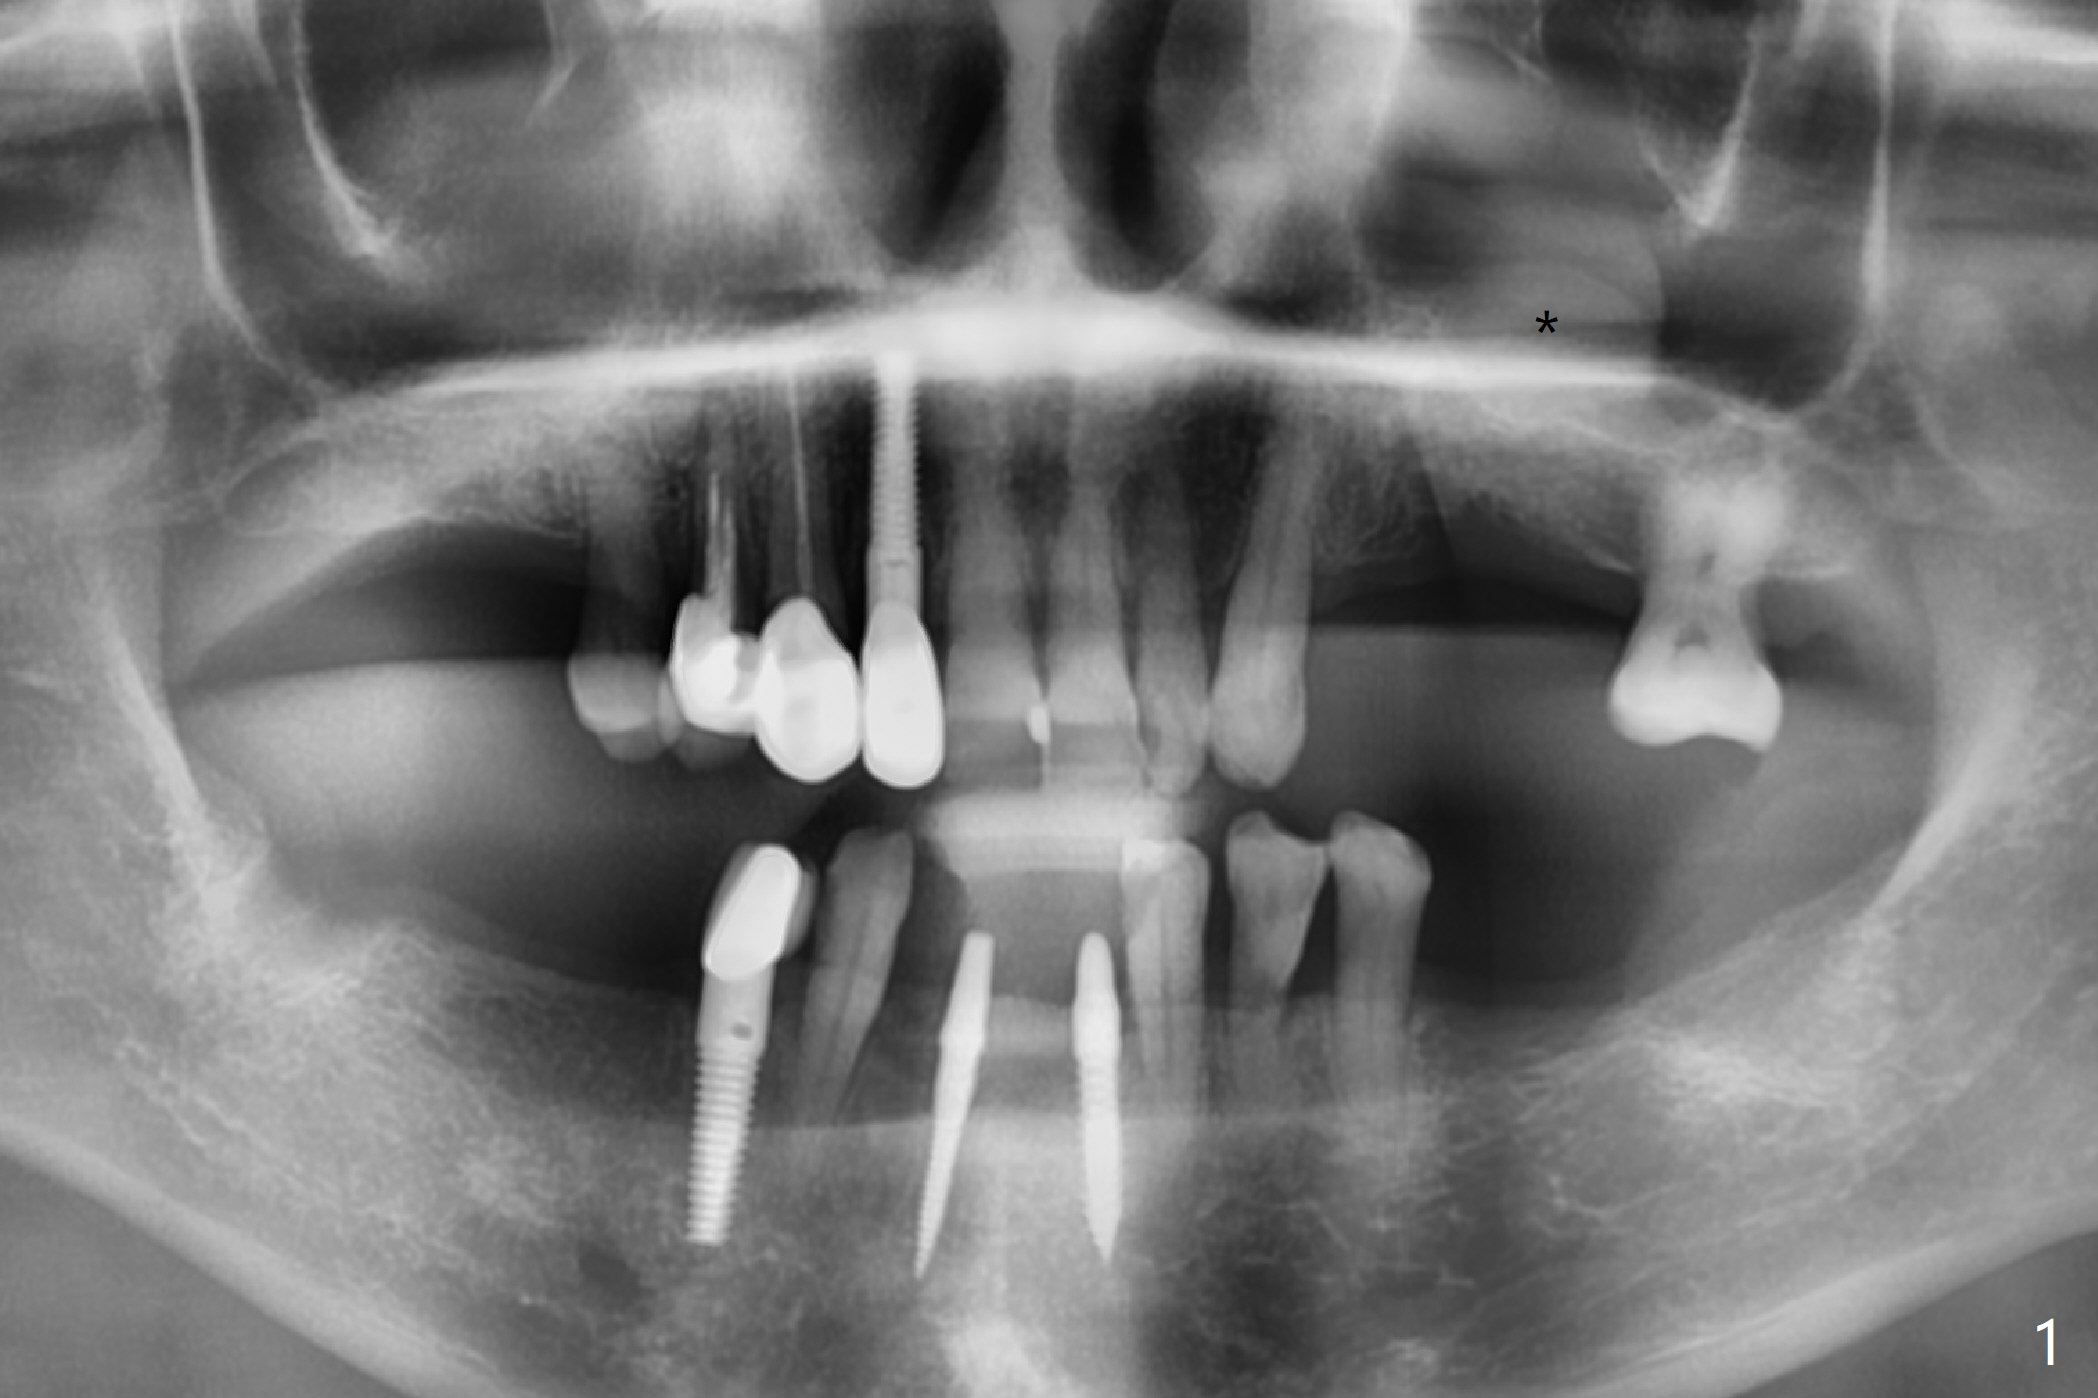

A 74-year-old woman agrees to have implants at #12,14 (for FPD),18 and 19 with guide. Bone height is limited in the molars (Fig.2,3). There is a polyp in the left sinus (Fig.1 *).